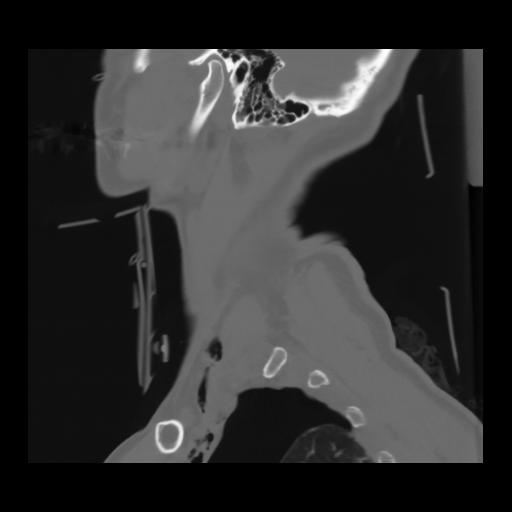

14 P.BLANDAS,,Sagittal,2.000,P.BLANDAS,Sagittal,